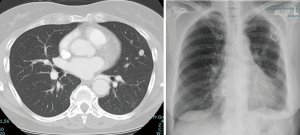

VATS wedge resection is the recommended approach for isolated unilateral or bilateral metastases with peripherally located nodules (<2 cm) as well as for peripherally located two unilateral metastases in multiple segments/lobes. VATS anatomical resection is to be favored in isolated metastases (>2 cm) or centrally located or KRAS-mutated CRC and in two unilateral metastases with central location in a single segment/lobe. In case of more than 3 metastases or central location of two metastases in multiple segments/lobes, a thoracotomy with bimanual palpation and a parenchyma sparing laser (Video 1) or electrocautery enucleation is the approach of choice. A radical lymphadenectomy is recommended in all anatomical resections as well as metastasis of renal cell carcinoma (RCC) and CRC. In all other patient groups, lymph node sampling is sufficient (Figure 3). The long-term outcomes after metastasectomy equally depend on the morphology and histology of the metastasis as well as the surgical skills and the type of operative resection approach employed. It is vital for an optimal outcome to individualize a concept for the patient based on the aforementioned characteristics.

VATS has an increasingly important role in lung metastases surgery. Minimally invasive approach allows enhanced recovery protocols and is associated with less pain, less complications, better functional outcome and shorter hospital length of stay. Its usefulness however, is limited when multiple or deeper parenchymal lesions have to be resected (Figure 2). Pulmonary metastasectomy by open thoracotomy is the standard procedure for 2 or more ipsilateral lesions, allowing manual palpation of the entire lung and thereby identifying additional undetected lesions. VATS approach is an alternative in special situations and should be preceded by a detailed radiological evaluation and when available using techniques such as MIP and CAD to increase detection sensitivity.